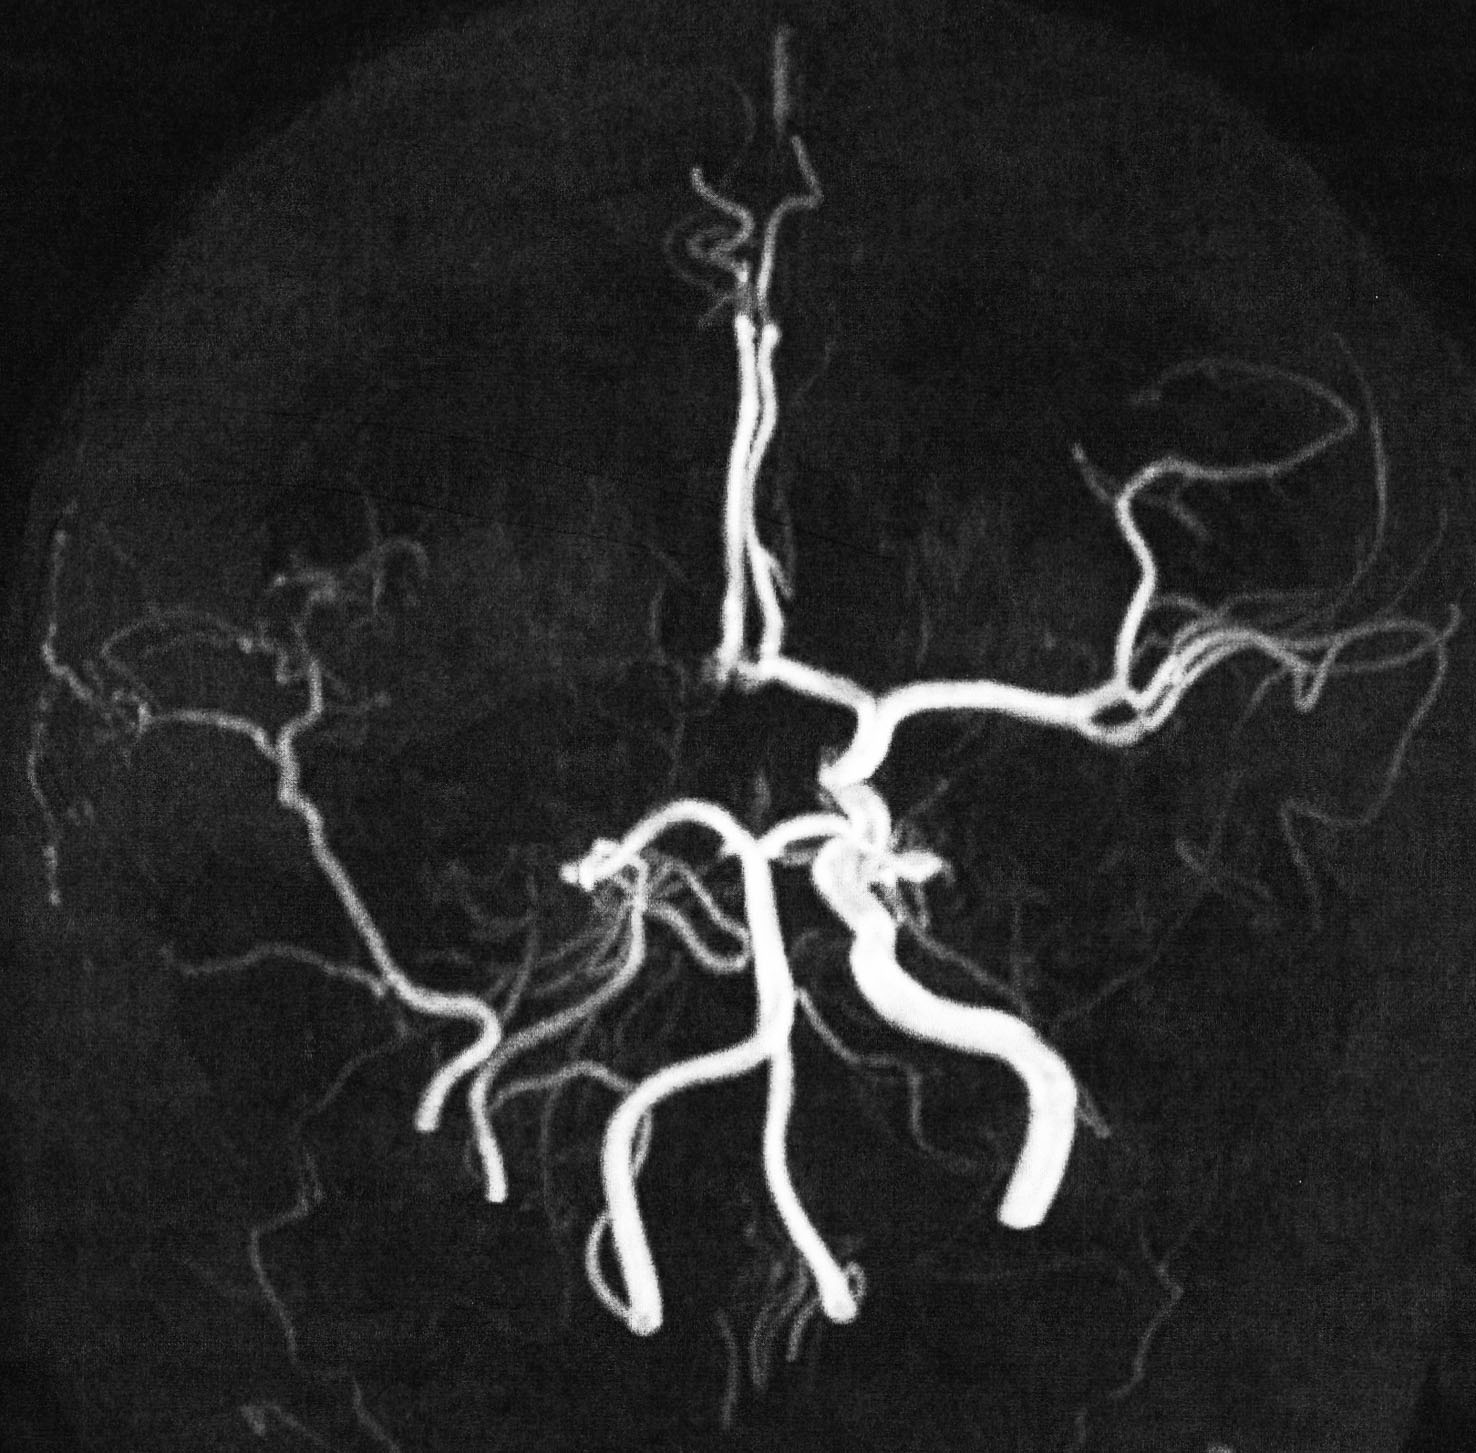

小児のクラニオ:放射線治療後の内頸動脈閉塞と脳動脈瘤の発生

4歳の時に頭蓋咽頭腫に対して50グレイの分割照射を受けました。両側の内頸動脈と前交通動脈が被曝しています。16歳(12年後)に左片麻痺の虚血発作を生じました。右内頸動脈が閉塞してウィルス動脈輪閉塞(モヤモヤ病)になっていました。前交通動脈に動脈瘤(赤矢印)もできていました。小児の頭蓋咽頭腫への放射線治療ではかなり高率に閉塞性脳血管障害を生じるのですが,治療後10年以上がたってから起るので,治療を行った医師はそれをみることはほとんどありません。

小児のクラニオ:放射線治療後の脳梗塞

3歳の時に鞍上部クラニオに40グレイの放射線治療を受けました。31歳(28年後)で右前頭葉に脳梗塞を生じました。右内頸動脈と左前大脳動脈が閉塞したウィルス動脈輪閉塞症(モヤモヤ病)になっています。右の中硬膜動脈から右大脳に血流が入っています。

5歳でガンマナイフ,8歳と10歳の時にサイバーナイフ治療を受けました。右内頸動脈が閉塞してウィルス動脈輪閉塞(モヤモヤ病)になりました。この画像は10歳時のものです。右中硬膜動脈から右の前頭葉と側頭葉に血流が入っていてモヤモヤ病の病態です。脳虚血発作や脳梗塞はない無症候性のものです。

ガンマナイフやサイバーナイフなどの高線量照射では,動脈閉塞は多分割照射よりも早く生じます。